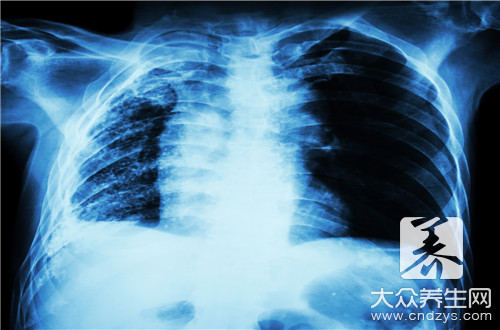

在生活中,潤肺的食物是比較多的,比如豆漿、毛肚血湯以及鴨肉粥等,還有一些中藥材也是可以潤肺的,大家可以在平時適當的吃一些調節肺部。因為肺部我們身體呼吸作用主要的器官,如果肺部功能下降,會影響我們的血液的流通,從而引起支氣管炎等肺部疾病,所以大家可以了解一些潤肺的食物。

總結:通過本文我們知道環境對我們肺部的影響是很大的,如果出現肺不好的情況,除了注意環境以外還需要注意飲食,除了以上食物對肺有好處之外,胡蘿蔔、木耳等蔬菜多吃也是對肺有益的。另外飲食清淡以及多喝水也是很好的清肺方法,最好不要抽煙。